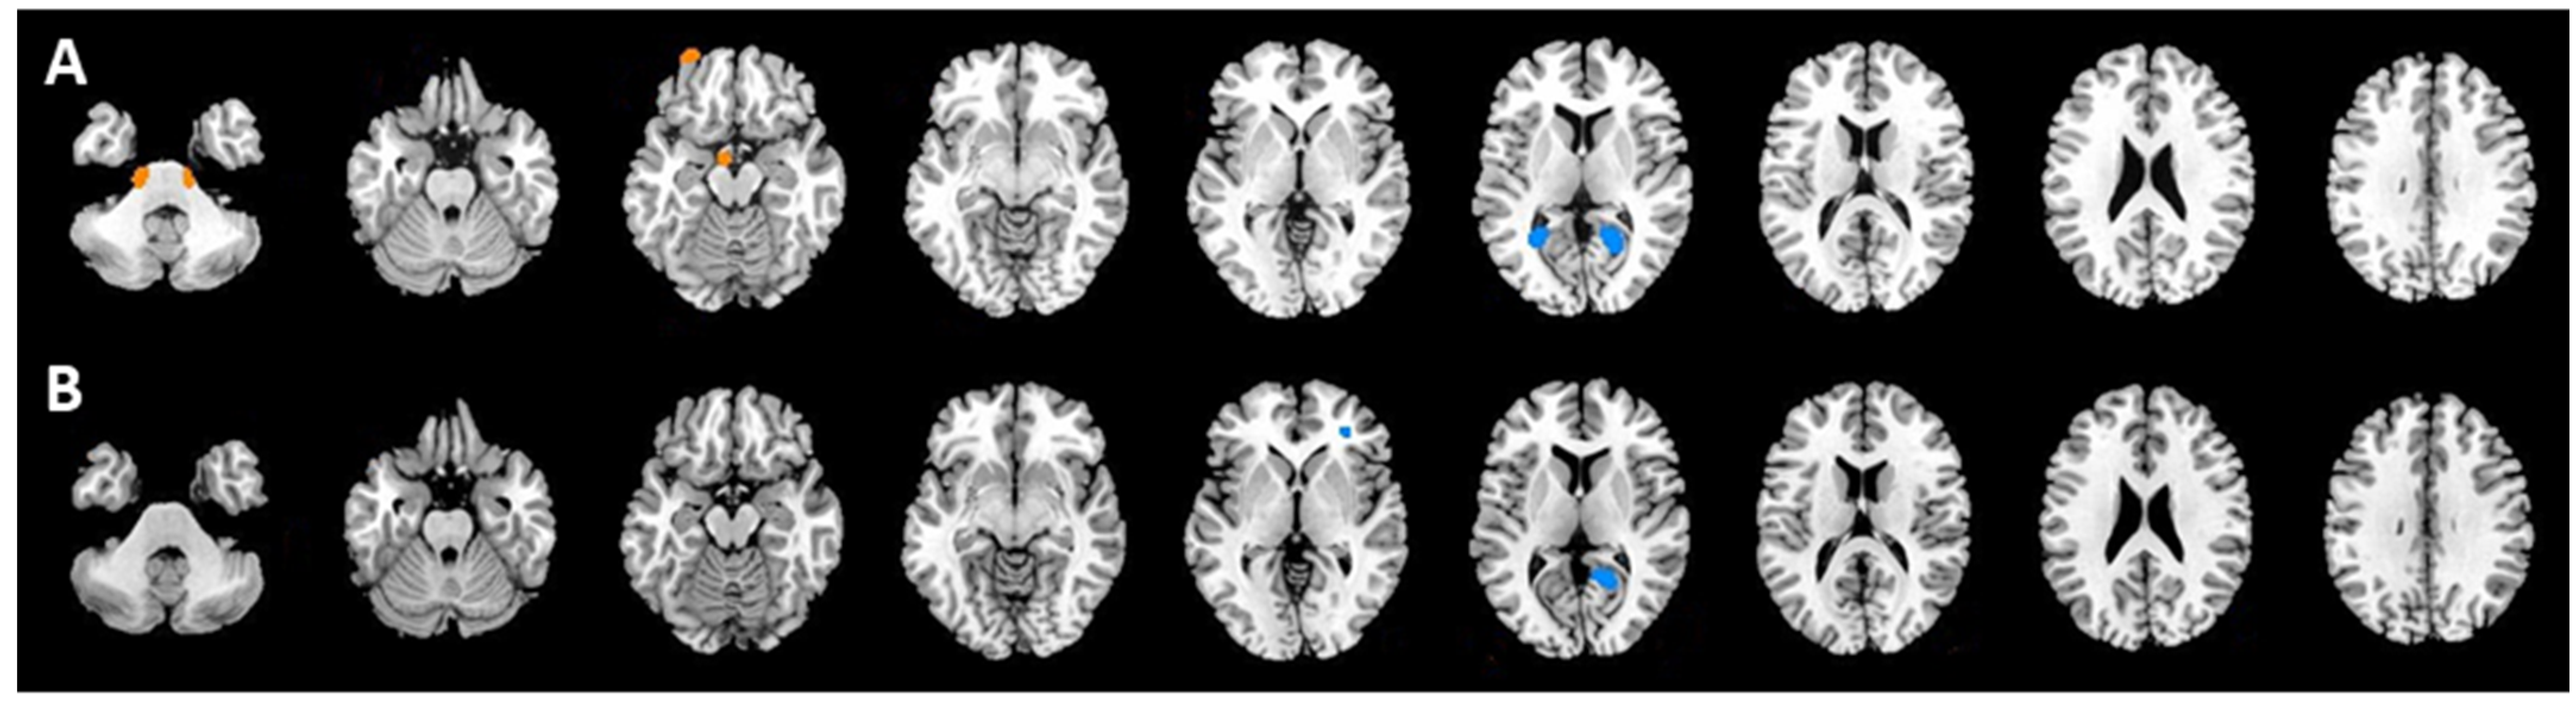

| Comparison | Region | Talairach Coordinates | T Score | p Values (Uncorrected) | ||

|---|---|---|---|---|---|---|

| x | y | z | ||||

| CR&NonCR (PET2) | ||||||

| hypermetabolism | Right pons 1 | 10 | −26 | −50 | 1.96 | 0.026 |

| Right pons 2 | 16 | −24 | −44 | 1.95 | 0.027 | |

| Left pons | −14 | −24 | −40 | 1.76 | 0.041 | |

| hypometabolism | Right lingual gyrus | 28 | −56 | 8 | 2.12 | 0.018 |

| Left lingual gyrus | −20 | −56 | 8 | 2.33 | 0.011 | |

| CR&NonCR (PET6) | ||||||

| hypometabolism | Left lingual gyrus | −18 | −54 | 8 | 2.30 | 0.011 |

| Left inferior frontal gyrus | −32 | −38 | 2 | 2.55 | 0.006 | |